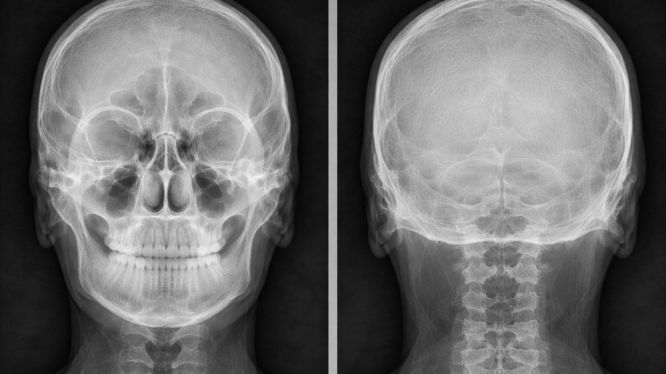

🔹 Radiografía antero-posterior

También se solicita para:

• Localizar fracturas

• Detectar quistes o tumores

• Evaluar zonas medias y posteriores del cráneo

Radiografía antero-posterior

🔹 Radiografía postero-anterior

Permite un análisis completo del cráneo para:

• Valorar asimetrías

• Densidad ósea

• Patologías generales